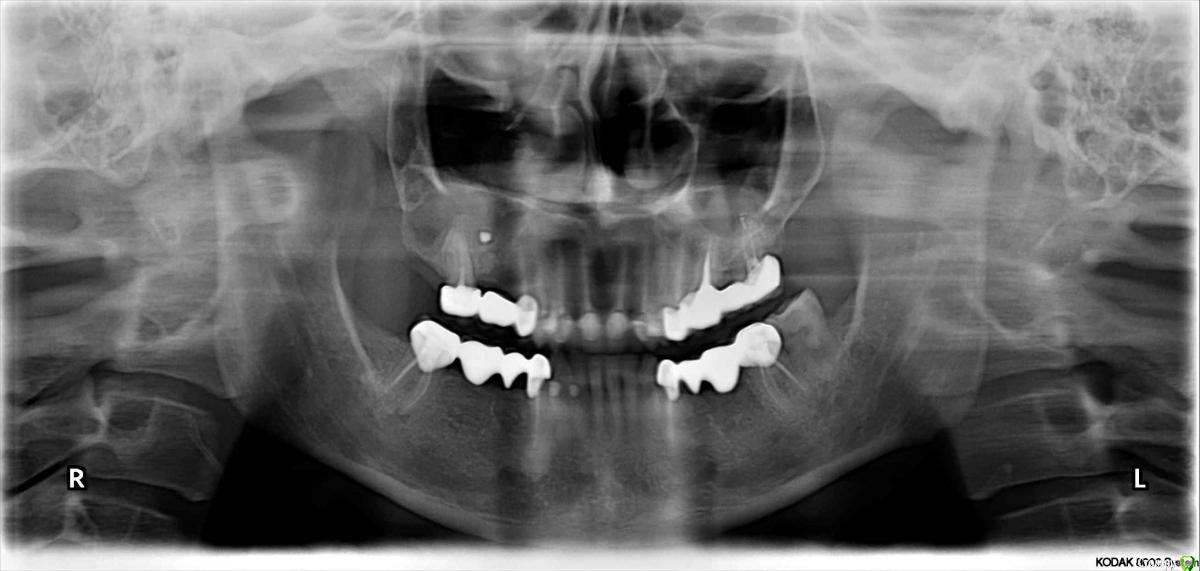

lazzal Опубликовано 29 октября, 2015 Поделиться Опубликовано 29 октября, 2015 Уважаемые хирурги-имплантологи, подскажите пожалуйста возможна ли в моем случае имплантация отсутствующих зубов верхней челюсти, какими имплантами (может мини?) и какая должна быть подготовка -может костная пластика? и возможна ли она? прилагаю 3 панорамных снимка - первый сделан в 2012 году сразу после протезирования всех зубов (делали одномоментно и верх и низ - половина зубов была абсолютно здорова, поднимали прикус таким образом, линия улыбки - безметалловая керамика), второй в апреле 2014г до удаления зуба на в.ч., третий в октябре 2015 (3 дня назад). От чего может быть такая убыль костной ткани? врач говорит, что теперь только бюгельный протез, может он с такими случаями не сталкивался? Возможно, опытные врачи на этом форуме увидят еще какие-то проблемы с зубами или деснами, на которые стоит обратить внимание. мне всего 32 года, я очень симпатичная внешне, очень хочется продлить жизнь своим зубам и не иметь проблем с жеванием. Заранее огромное спасибо всем откликнувшимся, буду Вам безмерно благодарна. Ссылка на комментарий